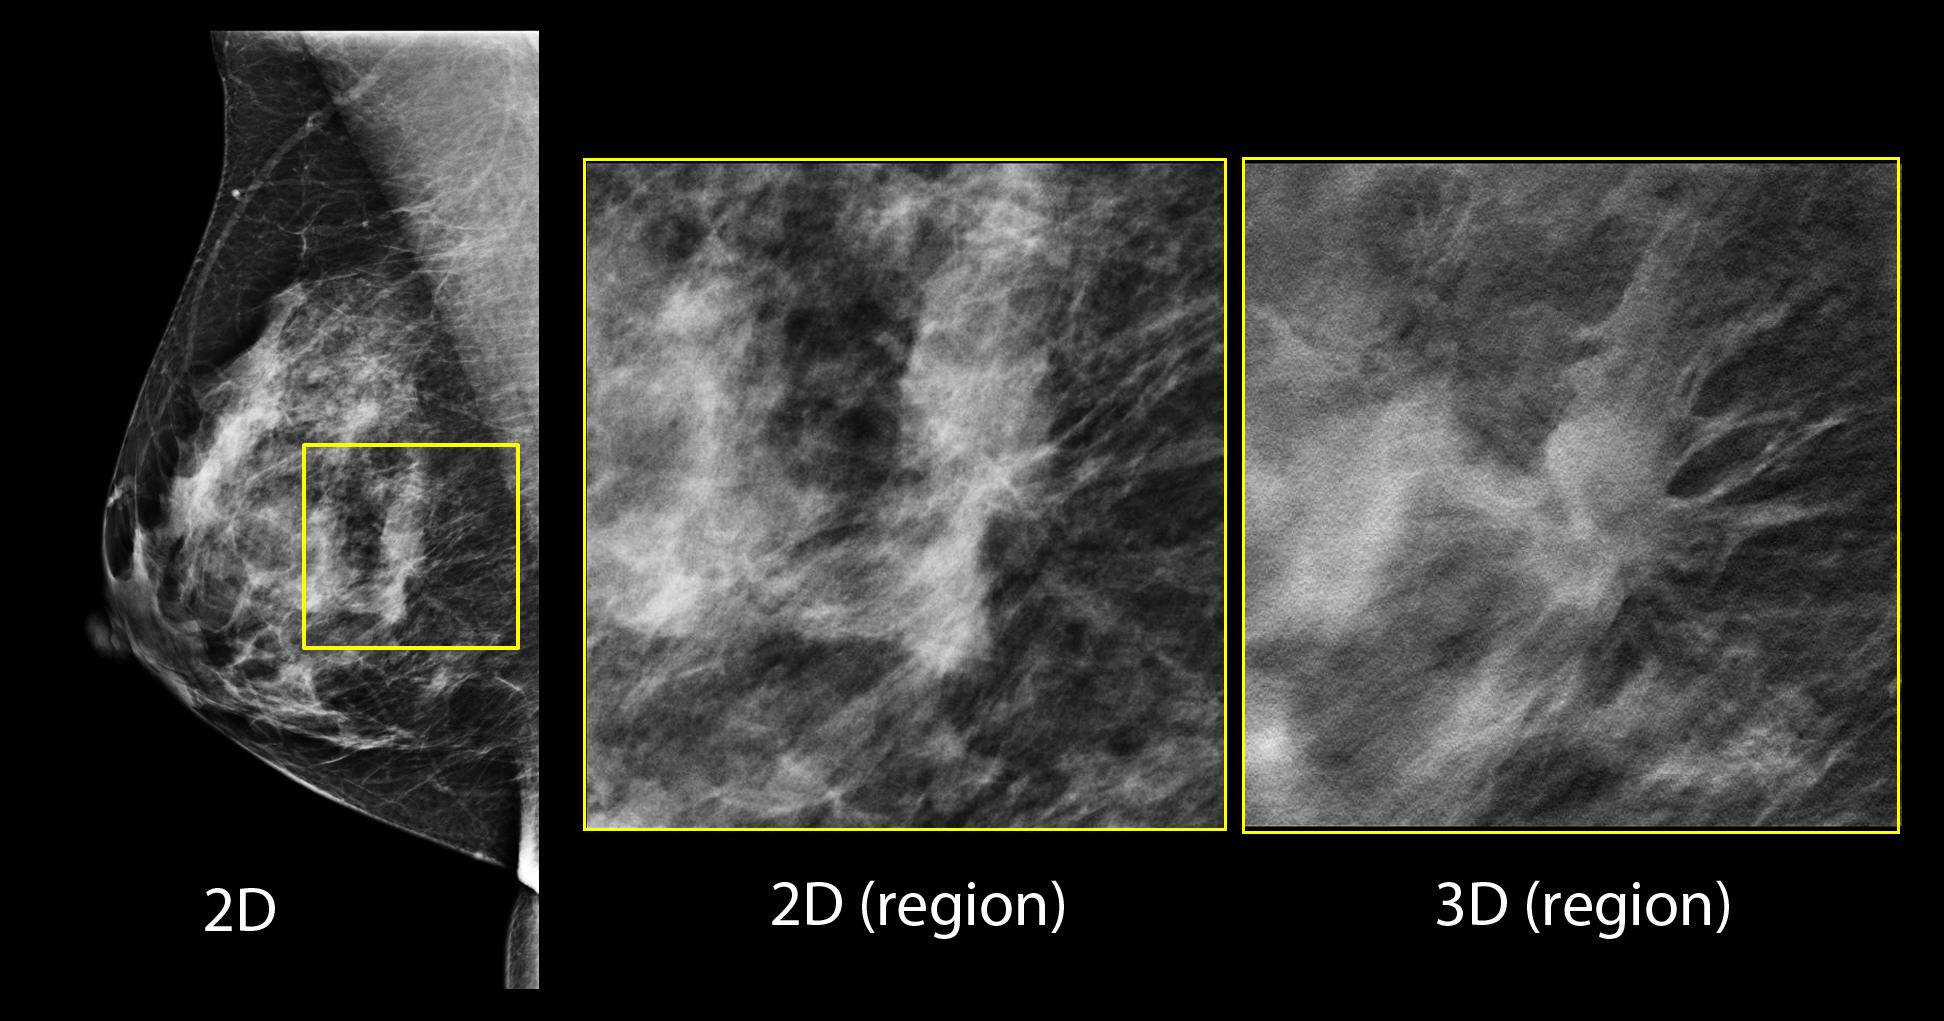

Better visibility

Designed to improve visibility of fine details for greater diagnostic confidence.*